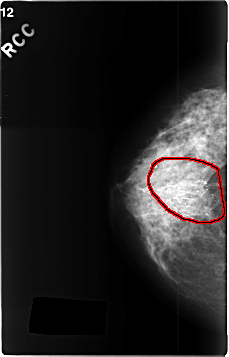

FILE: C_0341_1.RIGHT_CC.OVERLAY

TOTAL_ABNORMALITIES 1

ABNORMALITY 1

LESION_TYPE CALCIFICATION TYPE FINE_LINEAR_BRANCHING DISTRIBUTION SEGMENTAL

ASSESSMENT 5

SUBTLETY 5

PATHOLOGY MALIGNANT

TOTAL_OUTLINES 1

BOUNDARY